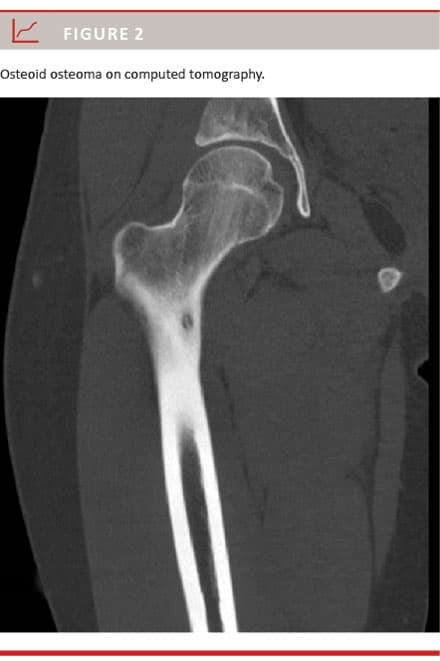

The radiological diagnosis is based on conventional radiography, the characteristic feature of which is an oval radiolucency area representing the nidus sur-

rounded by reactive bone sclerosis (Figure 1). The diagnosis may also be established by computed tomography (CT) where the characteristic appearance of OO is a low-attenuation nidus with a varying amount of bone sclerosis (Figure 2). Occasionally magnetic resonance imaging (MRI) and rarely bone scintigraphy are preformed to confirm the diagnosis [4, 6]. Bone scintigraphy is made with Tc-99-labelled diphosphonates, which accumulate in areas with increased osteoblastic activity and bone turnover and therefore have a markedly increased uptake in the nidus [4].